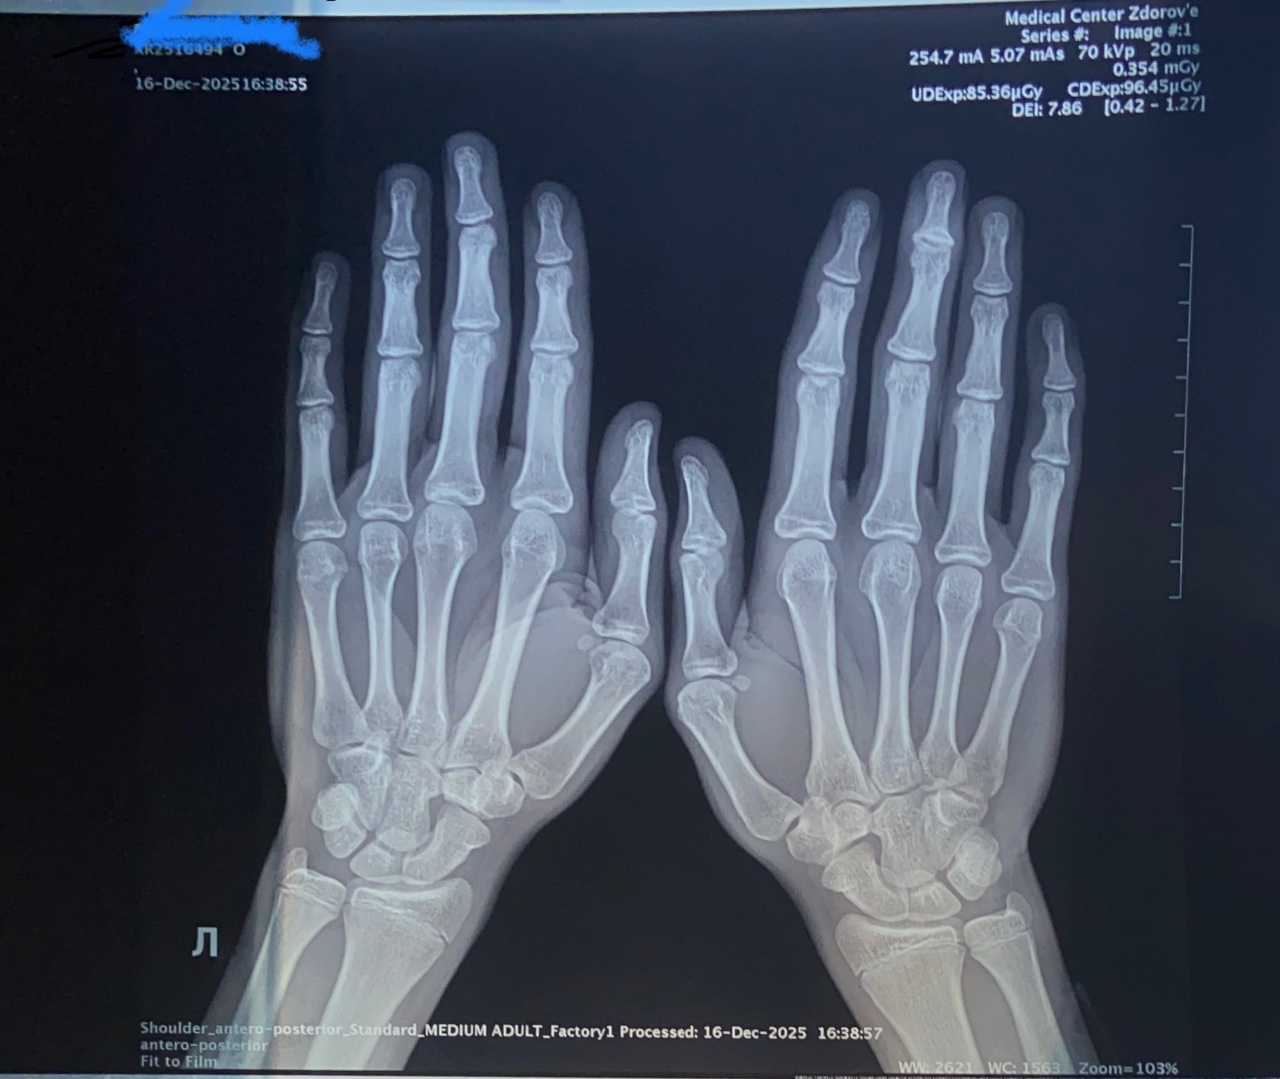

Здравствуйте, сделал рентген кистей, чтобы узнать ростовой потенциал. Мне сказали, что зоны роста эпифизов фаланг, локтевой и лучевой кости открыты. У меня рост 183-184, рост отца 194, матери-165. Так же в подростковый период у меня не было режима сна(ложился в 1-2 часа ночи, редко бывало, что не спал до утра), часть времени плохо питался. Так же добавлю, что отец в 15.5 был 187, рос он, получается, долго, до 20-21. Рентген двух кистей в прямой проекции прикрепил фото